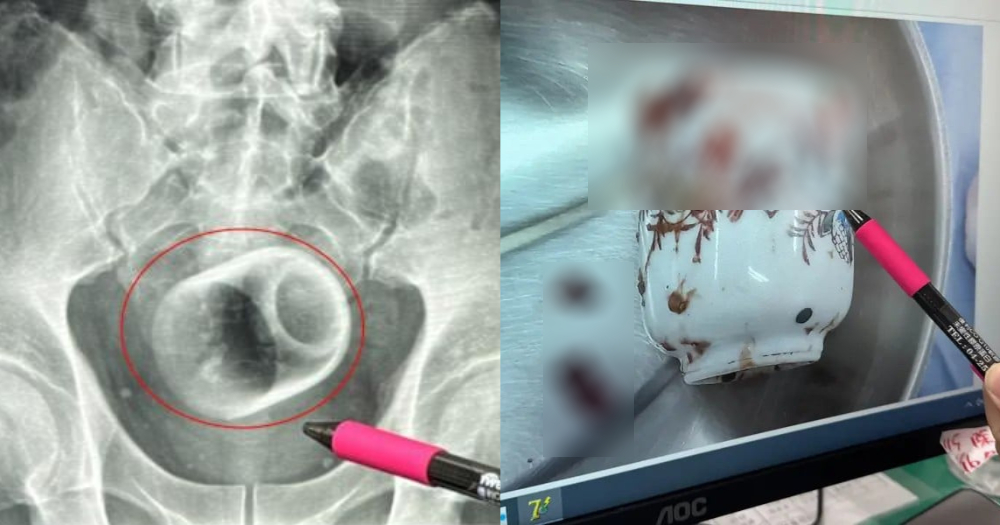

Man in Taiwan somehow gets 8cm by 6cm ceramic cup in bottom, claims it got there 'by accident'

A man in Taiwan was found with a ceramic cup, measuring 8cm tall and 6cm wide, in his anus during an X-ray scan.

X-rays revealed the cup facing down in the pelvic cavity.

They finally removed the cup in an open surgery on the man's abdomen, while creating an artificial stoma to allow him to defecate.